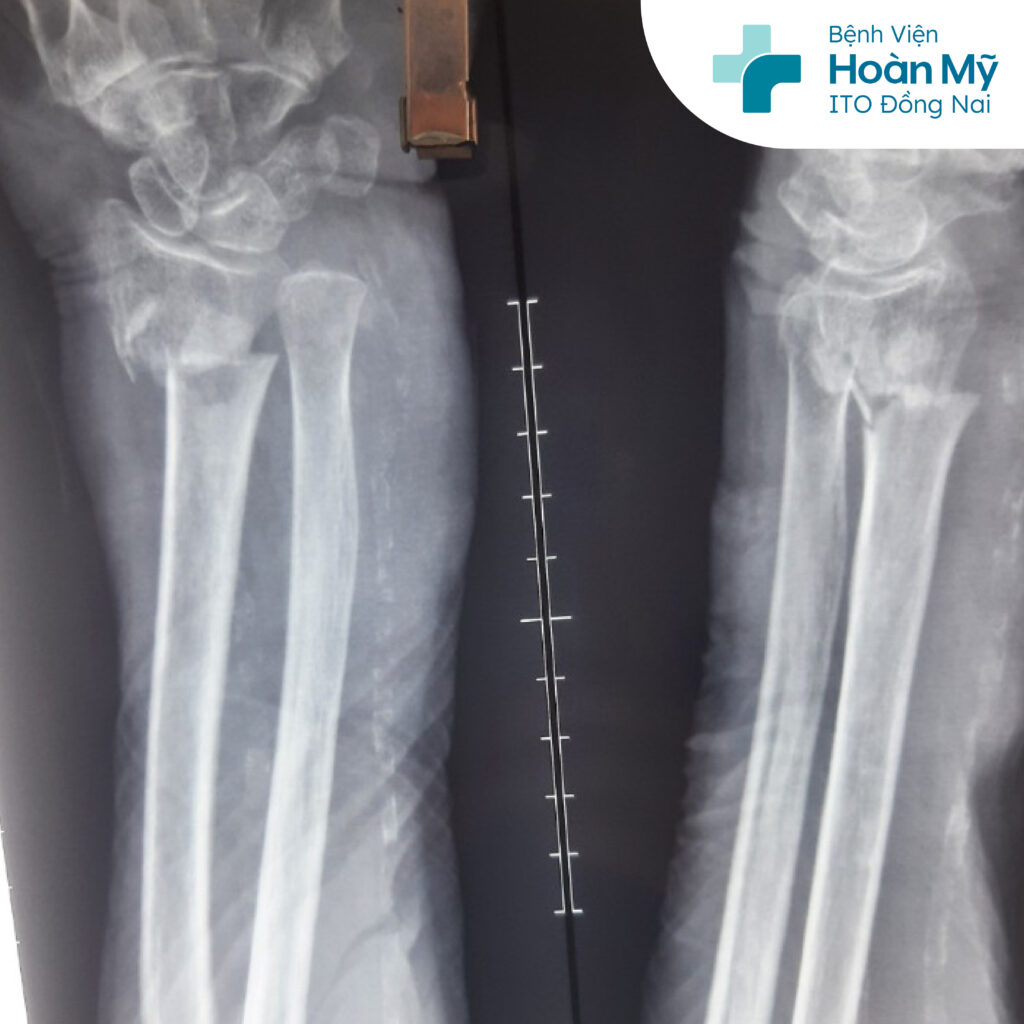

Cụ bà N.T.T, 103 tuổi, ngụ tại Định Quán, Đồng Nai, bị té ngã khi vừa đi tắm ra tại nhà. Mặc dù có gậy hỗ trợ nhưng vì trơn trượt cụ chống tay trái xuống nền. Sau té, cụ T bị đau nhiều ở cẳng tay trái nên được người nhà đưa lên bệnh viện Hoàn Mỹ ITO Đồng Nai cấp cứu. Qua thăm khám và chụp X-quang kết quả cụ bị gãy hở đầu dưới xương quay tay trái, với nhiều bệnh lý nội khoa đi kèm là cao huyết áp, tiểu đường, hở van tim, suy dinh dưỡng…

Nhận định đây là bệnh nhân tuổi cao hiếm gặp, nguy cơ xảy ra rủi ro trong và sau phẫu thuật cao, nên các bác sĩ đã hội chẩn giữa nhiều chuyên khoa để tầm soát bệnh lý đi kèm và tiên lượng trước nguy cơ để có phương án phẫu thuật đảm bảo an toàn nhất cho người bệnh. Bệnh nhân được Bs CKI Hoàng Đức Mạnh - Khoa Chấn thương chỉnh hình và ekip tiến hành phẫu thuật kết hợp xương bằng đinh kirschner.

Hình ảnh X-Quang gãy đầu dưới xương quay